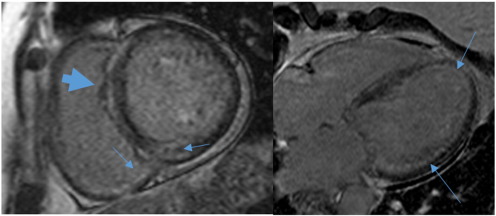

Fig. B.1.

Pre-PBSCT echocardiogram.

Fig. B.2.

Post-PBSCT echocardiogram.

Echocardiography suggested statistically significant regression in the cardiac amyloid process, similar to what had previously been reported [18]. Wall thickness significantly reduced, atrial size shrunk, and measures of diastolic function improved (see Fig. B.1 ;  Fig. B.2). The ejection fraction did not significantly change. Myocardial strain analysis at late follow-up suggested better global longitudinal strain in this highly selected group of survivors, than many cardiac amyloid studies have suggested (the global longitudinal strain was more negative than previously reported for cardiac amyloid patients) [13]; [25] ;  [26]. The mean global longitudinal strain was − 16%. The classical bulls-eye pattern of cardiac amyloidosis was only seen in 50% of these patients [13] ;  [26] (see Fig. B.3 and Table A.2). Strain had not been assessed before PBSCT for any of the patients in this study.